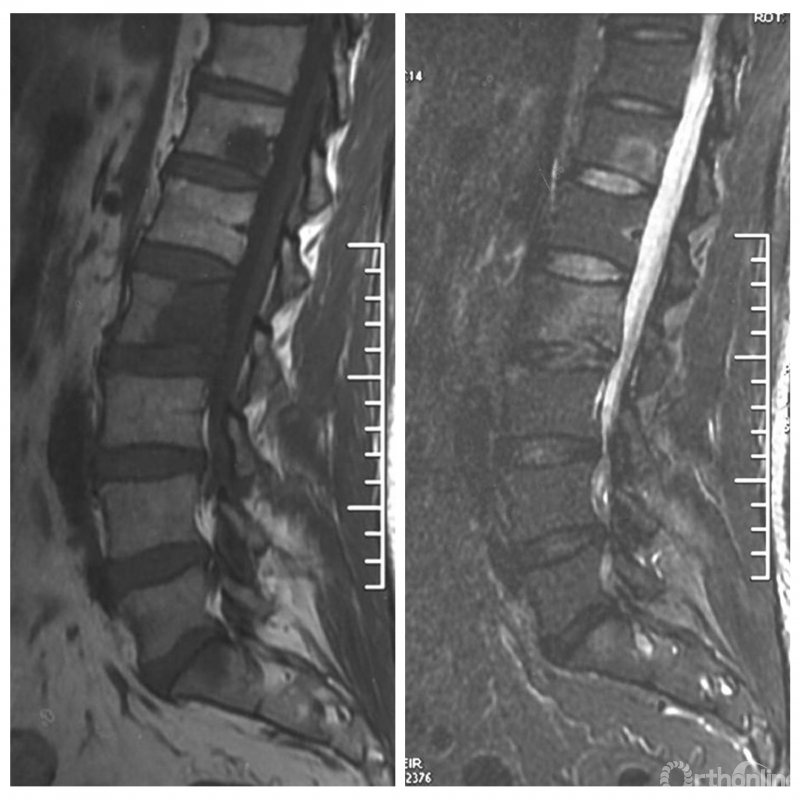

患者腰椎转移瘤术后9个月,因“腰痛伴右下肢疼痛麻木2个月”再次入院。既往在PVP术后曾行化疗及服用埃克替尼靶向药物维持治疗,查体一般状况良好,自主行走,右大腿前外侧麻木。

入院影像学资料

经脊柱转移瘤专业评估,ESCC分级为Grade2,对放疗不敏感;SINS评分8分,中度不稳。Karnofsky功能状态评分90%,预计生存时间6个月。NOMS流程建议分离手术和SRS。

常规分离手术可进行360°脊髓减压,充分固定恢复脊柱稳定;但由于其暴露范围广泛,创伤较大,并不适宜患者当前治疗。

为进一步减少创伤,获得更好的综合疗效。骨采用经皮内固定的微创杂交技术,暨经皮内固定结合小切口分离手术,手术失血900ml,术后7天出院。